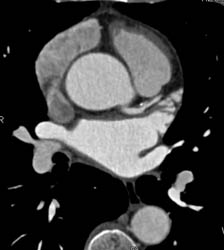

CASE NUMBER 1,252

Normal Trifurcation of Left Main Coronary Artery